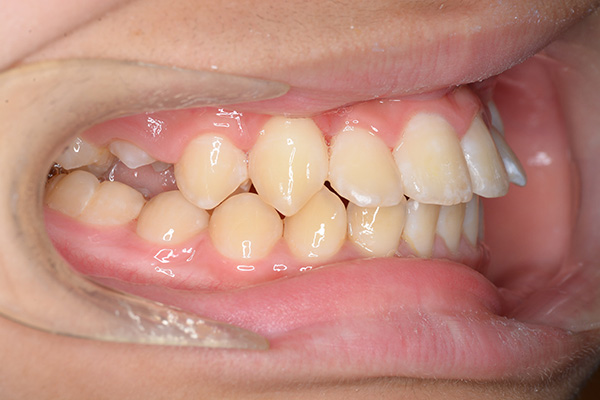

| 口腔内所見 | over jet 5.5mm,over bite 5.0mm,大臼歯関係はⅠ級 、Hellmanのdental ageはⅢBであり上突歯列を呈していた。 |

| パノラマ所見 | 上顎左右側犬歯は近心傾斜し側切歯歯根に重なるように認められた。 |

| 批評・予后 | 埋伏歯の牽引を行い位置異常の改善をした結果、適切な犬歯のガイドが得られ、ほぼ緊密な咬合となったように思う。口元の改善を希望された場合は小臼歯抜歯症例として本格矯正治療を行う予定である。 |